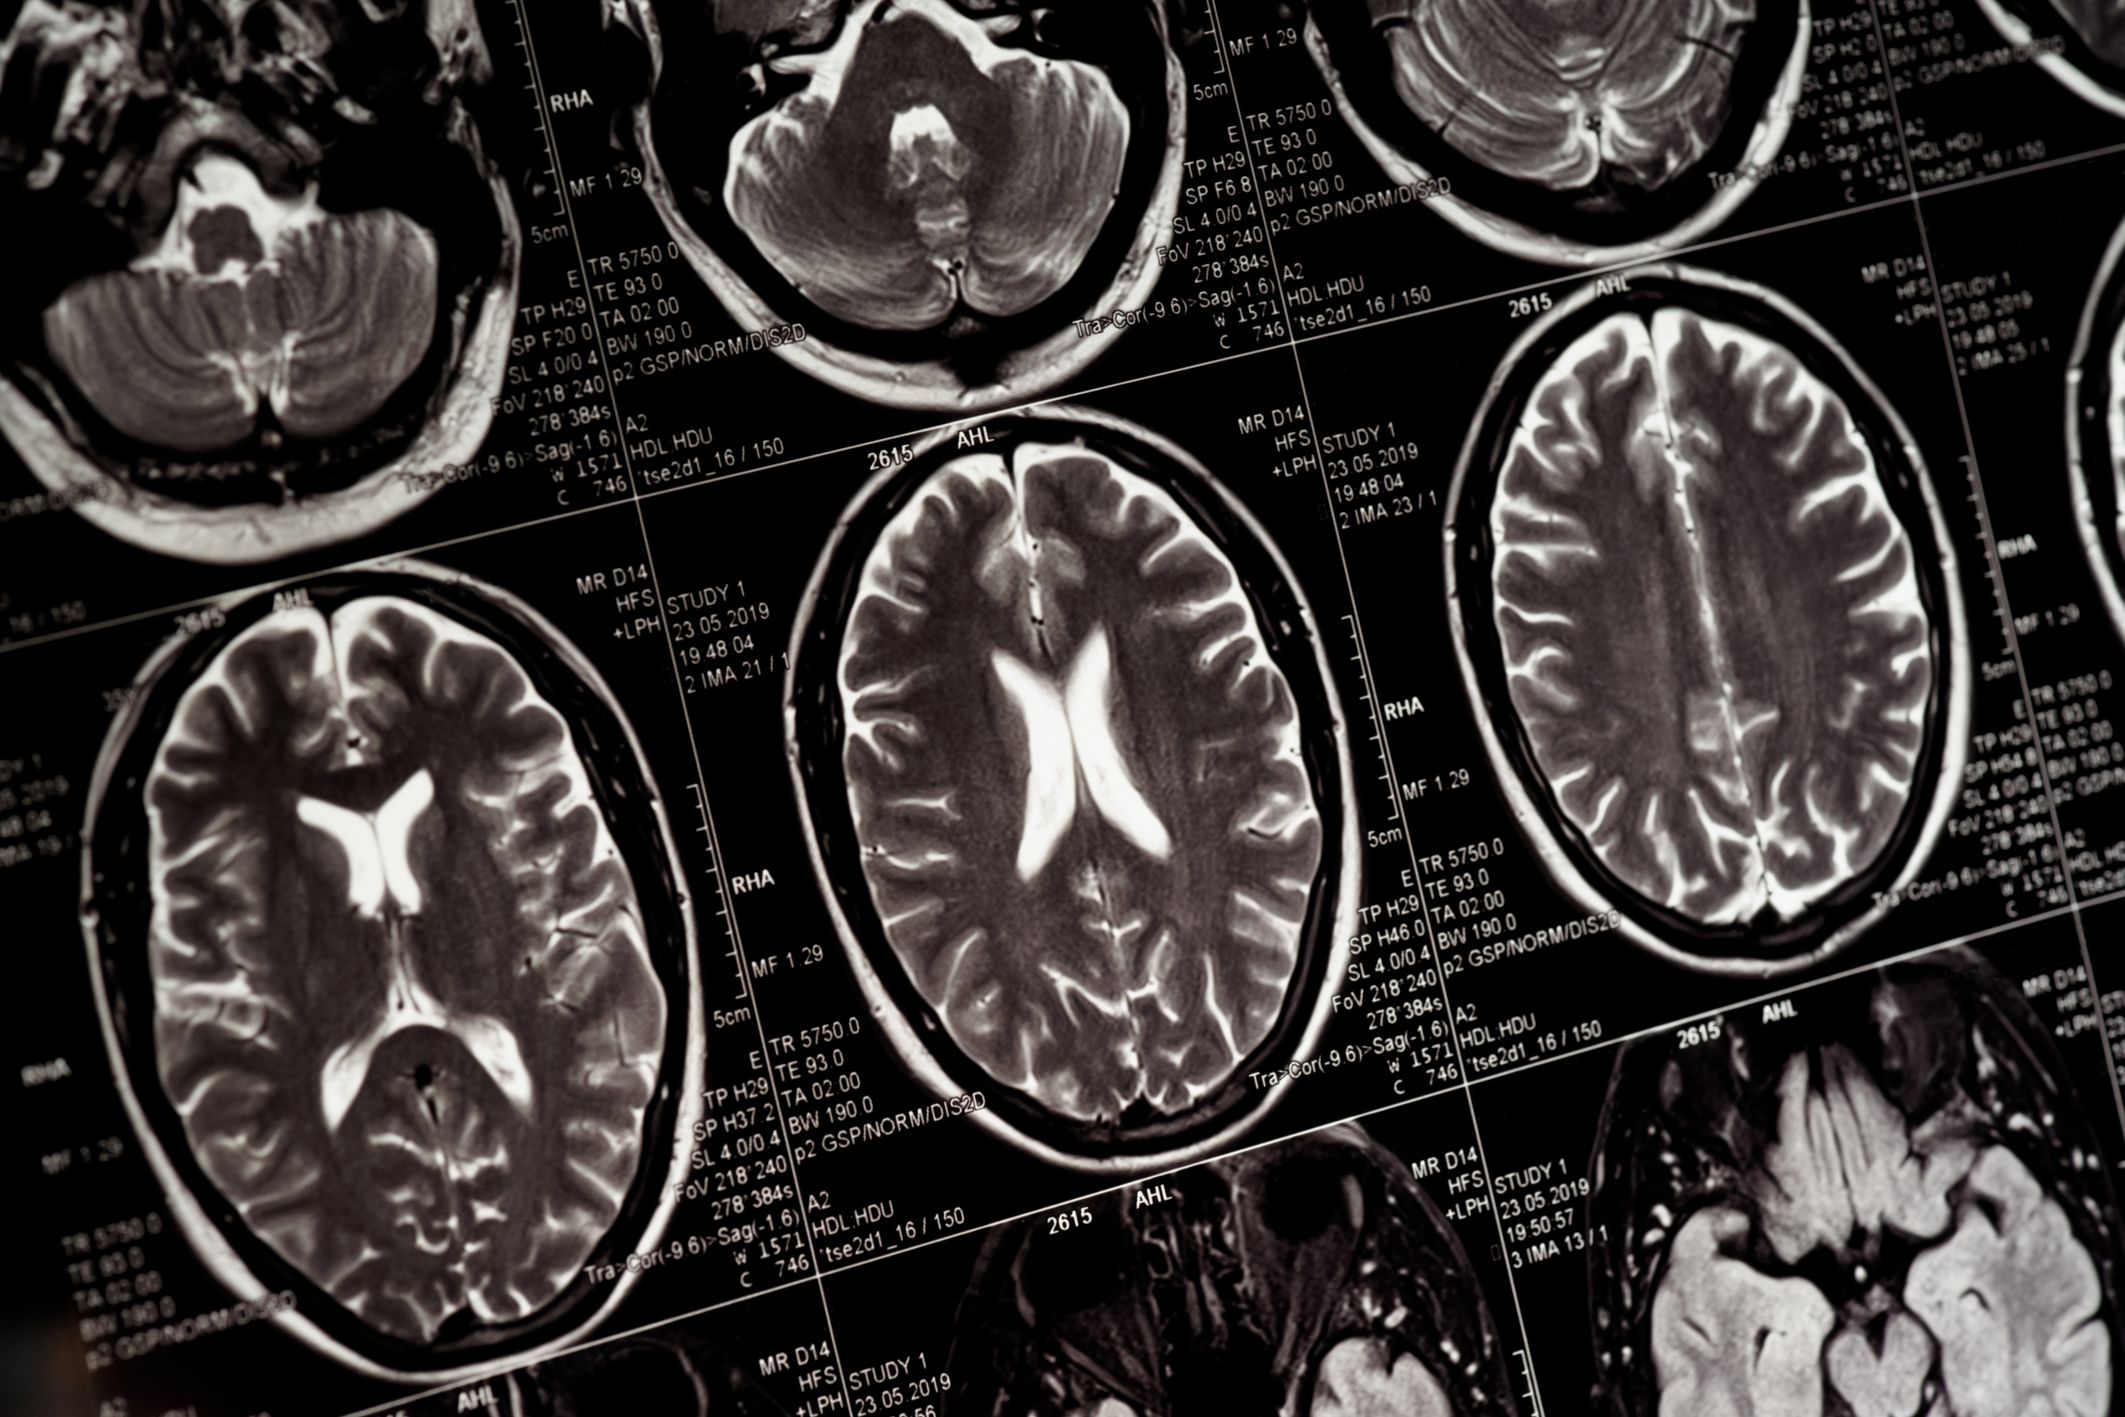

มหาวิทยาลัยเบนกูเรียนแห่งเนเกฟของอิสราเอล (Ben-Gurion University of the Negev - BGU) เปิดเผยเมื่อวันที่ 21 ธ.ค. 68 ว่าทีมนักวิจัยจากอิสราเอล รัสเซีย สาธารณรัฐเช็ก และเบลเยียม ค้นพบกลไกของโปรตีนชนิดหนึ่งที่มีชื่อว่า “เซอร์ทูอิน 6” (SIRT6) สามารถช่วยปกป้องสมองจากความเสียหายที่เกิดขึ้นตามวัย

การศึกษาดังกล่าว ซึ่งเผยแพร่ในวารสารเนเจอร์ คอมมูนิเคชันส์ (Nature Communications) ระบุว่าเซอร์ทูอิน 6 ทำหน้าที่ควบคุมการใช้ทริปโตเฟน (tryptophan) ในสมอง ซึ่งเป็นสารสำคัญที่ช่วยสร้างพลังงานและสารเคมีสำคัญอย่างเซโรโทนิน และเมลาโทนิน

ทริปโตเฟนมักถูกเรียกว่าเป็น “โมเลกุลแห่งการนอนหลับ” แต่ยังมีบทบาทต่ออารมณ์ การเรียนรู้ และสุขภาพของสมอง เมื่อเข้าสู่วัยชราหรือเกิดโรคทางสมองบางชนิด สมดุลของการใช้ทริปโตเฟนจะถูกรบกวน ส่งผลให้การผลิตเซโรโทนินและเมลาโทนินลดลง ขณะเดียวกันยังทำให้เกิดผลตามมาที่เป็นอันตรายซึ่งเป็นพิษต่อเซลล์ประสาท

ทีมนักวิจัยใช้แบบจำลองการทดลองในเซลล์มนุษย์ หนู และแมลงหวี่เพื่อศึกษากระบวนการดังกล่าว โดยพบว่าเมื่อระดับเซอร์ทูอิน 6 ลดลง ทริปโตเฟนจะถูกนำไปใช้ในการผลิตพลังงานมากขึ้น ส่งผลให้เกิดองค์ประกอบสารพิษ และทำให้สมองขาดสารสื่อประสาทที่ช่วยปกป้องสมอง

นอกจากนี้ การศึกษายังพบวิธีการที่จะแก้ไขความเสียหายดังกล่าว โดยการยับยั้งเอนไซม์อีกชนิดหนึ่งที่เรียกว่าทีดีโอ2 (TDO2) ในแมลงหวี่ที่ขาดเซอร์ทูอิน 6 ยังสามารถลดการเกิดสารพิษ ปกป้องเนื้อเยื่อสมอง และช่วยให้การเคลื่อนไหวดีขึ้น ซึ่งผลการค้นพบนี้เปิดโอกาสใหม่ในการรักษาความผิดปกติของสมองที่เกี่ยวข้องกับวัย ปัญหาการนอนหลับ และการเปลี่ยนแปลงทางอารมณ์

ทั้งนี้ การมุ่งเป้าไปที่เซอร์ทูอิน 6 หรือทีดีโอ2 อาจช่วยปกป้องสมอง ฟื้นฟูสมดุลทางเคมีที่ดีต่อสุขภาพ และยกระดับคุณภาพชีวิตของผู้คนเมื่ออายุมากขึ้นได้